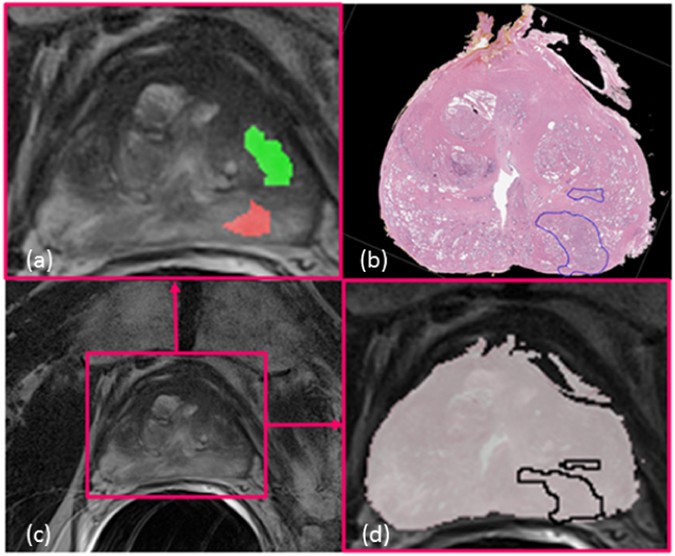

Figure 1

Illustration of a pair of corresponding in vivo prostate MRI (c) and ex vivo histology images (b). On panel (a) one can observe the cancer annotations made by two radiologists (green and red) unblinded to the corresponding histology images. The divergent annotations made by the two radiology readers, in spite of having access to the pathology images, suggests the need for accurate co-registration of pathology and radiology imaging in order to ascertain the ground truth extent for disease on radiology imaging ((d) the overlap registration visualization).